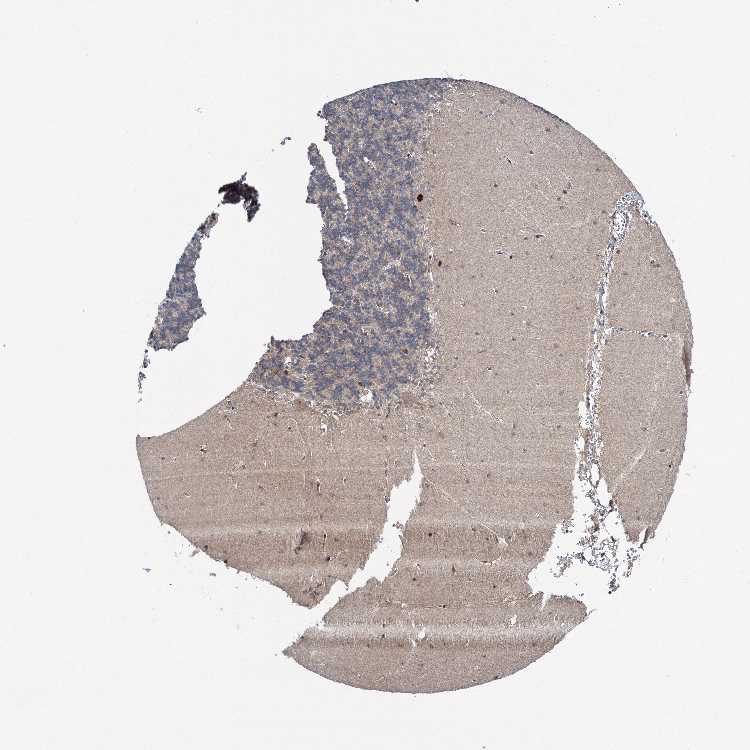

CEREBELLUM - Antibody stainingi

Antibody staining in the annotated cell types in the current human tissue is reported as not detected, low, medium, or high, based on conventional immunohistochemistry profiling in selected tissues. This score is based on the combination of the staining intensity and fraction of stained cells.

Each image is clickable and will lead to virtual microscopy that enables deeper exploration of all samples and also displays staining intensity scores, fraction scores and subcellular localization as well as patient and tissue information for each sample.

Antibody HPA037773

Purkinje cells High

Cells in granular layer Low

Cells in molecular layer Medium